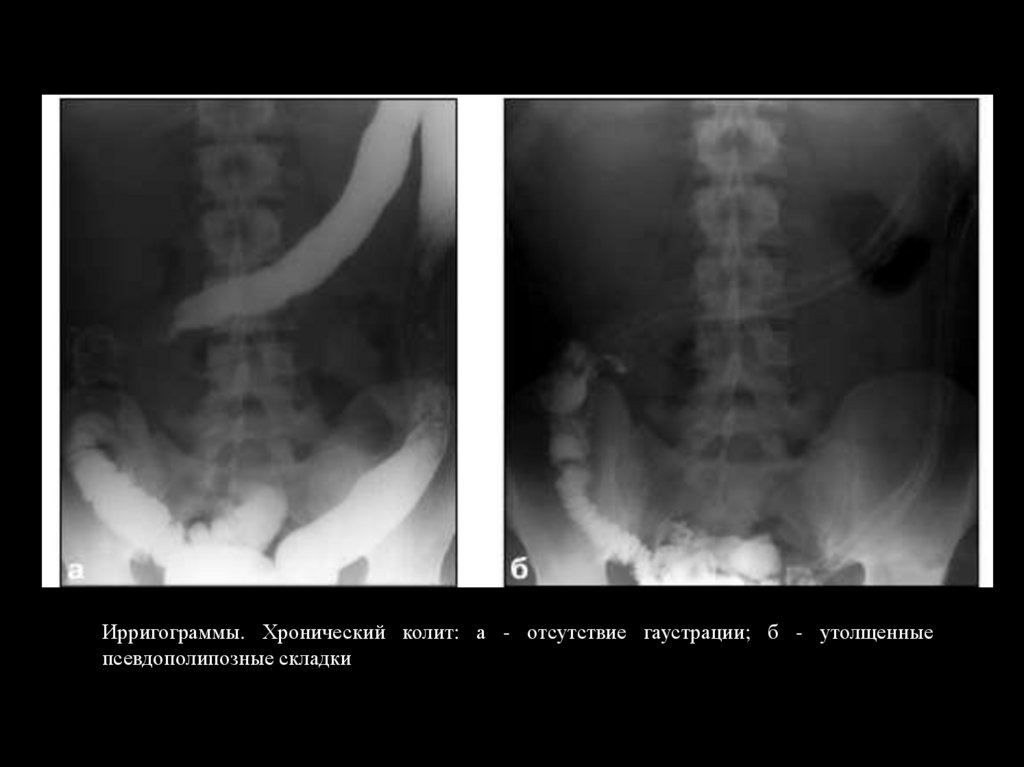

Ирригограммы. Хронический колит: а - отсутствие гаустрации; б - утолщенные

псевдополипозные складки